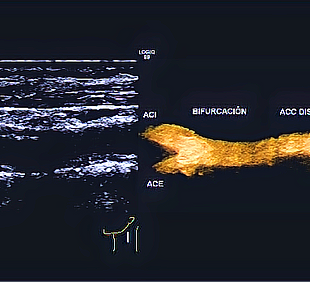

El Dr. Carlos Maury es un médico especialista en radiología e imagen diagnóstica y terapéutica. Experto en ultrasonido Doppler, Elastografía hepática, diagnóstico de enfermedades del hígado y en intervencionismo guiado por equipos de imagen médica.

Ultrasonido Doppler, Elastografía hepática, Intervención deportiva, Ultrasonido vascular, Biopsia de tiroides, biopsia de mama, entre otros estudios generales como ecografía obstétrica, de abdomen y pelvis.